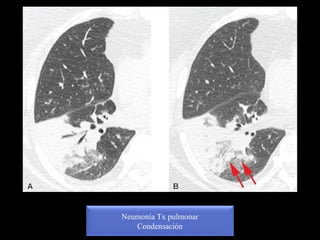

Neumonía Tx pulmonar

Condensación